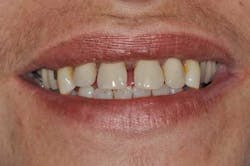

Fig. 2: Anterior teeth relationships prior to treatment

A 40-year-old woman, with no medical history except that she is a smoker (five cigarettes a day), is visiting us for an oral rehabilitation. Her chief complaints are teeth mobility and an esthetic concern since her maxillary front teeth are moving forward. The patient also suffers from dental anxiety.